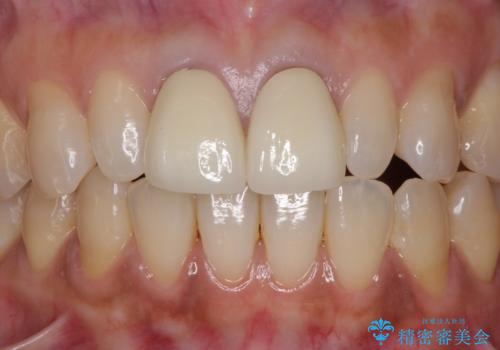

[フルジルコニアクラウン] 老朽化した銀歯を白く

![[フルジルコニアクラウン] 老朽化した銀歯を白くの症例 治療後](https://seimitsushinbi.jp/wp/wp-content/uploads/2020/05/60951366446f010978e24aba6c35e27e-500x350.jpg?v=1588518777)